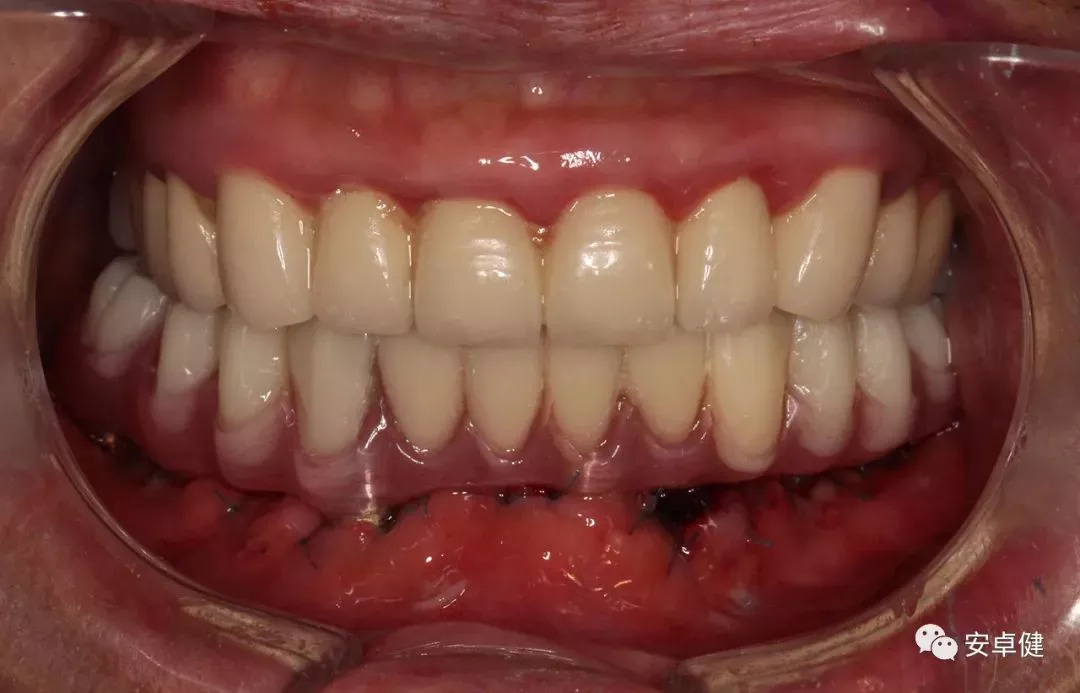

戴最终修复体正面咬合照

最终修复后8个月

戴牙后8个月复诊正面咬合照

• 随访可见患者口腔卫生状况可,牙龈无红肿;

• 下颌修复体状态良好,无修复体机械并发症;

• 种植体基台稳定性良好,无松动;

• 种植体无松动,周围无红肿、溢脓及疼痛表现;

• 正中、前伸及侧方咬合检查可见咬合印记分布均匀,咬合关系良好;

• 患者反映日常使用良好,舒适性佳,满意度高。